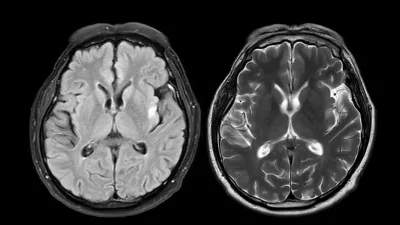

/ Foto: iStock